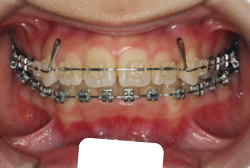

初診時の状態ですが、前歯の噛み合わせが逆転していて、下の前歯が外側に来て、上の前歯が裏側になっています。口元の様子ですが、前歯の重なり方が逆なので、唇の様子もそれを反映して、下唇が突出しています。反対咬合としてはかなり重症です。

分析してみると歯の傾き方に問題があるだけでなく、顎の骨の大きさと形にも問題があることが分かりました。ただし、骨の問題点が見つかったからと言って、必ずしも外科矯正になるわけではなく、このくらいの症状ですと、通常の矯正でもきれいに治すことができます。

診断の結果、下の前歯を正しい位置まで内側に入れていくためには、十分な隙間を確保することが避けられないと判断し、上の左右第二小臼歯と下の左右第一小臼歯は抜歯させて頂くことにしました。歯の本数は減りましたが、歯科医学的評価も大きく改善しましたし、審美的にも大幅な改善が見られますね。特に口元の様子が全然変わりました。